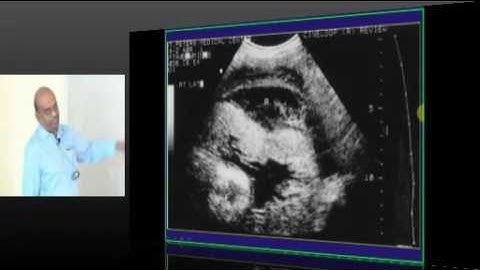

NEETPG Image based MCQ Mock Test Discussion 1495 Lec 01